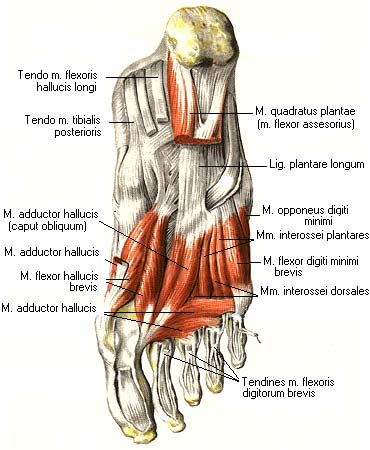

Анатомия подошвенной мышцы голени: подробное рассмотрение